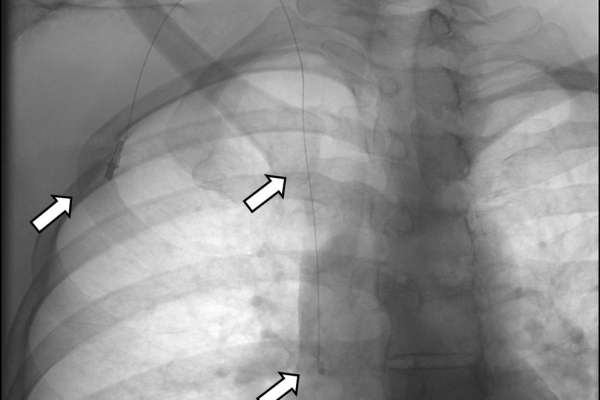

- Τα Port-a-Caths είναι εμφυτεύσιμοι κεντρικοί φλεβικοί καθετήρες με τύμπανο που τοποθετούνται διαδερμικά συνηθέστερα στο πρόσθιο θωρακικό τοίχωμα και ενώνονται μέσω υποδόριου τούνελ με την έσω σφαγίτιδα φλέβα. Η τοποθέτησή τους γίνεται στην αγγειογραφική σουίτα σε συνθήκες αποστείρωσης και με τη βοήθεια υπερηχογραφικού ελέγχου. Το Port-a-Cath είναι μια υποδόρια συσκευή, που δεν περιορίζει τις καθημερινές δραστηριότητεςκαι δεν απαιτεί συχνή φροντίδα. Ο ογκολογικός ασθενής μπορεί να κάνει άφοβα μπάνιο ακόμα και στη θάλασσα. Οι κίνδυνοι επιμόλυνσης και θρόμβωσης του καθετήρα είναι πολύ χαμηλοί, ενώ η διάρκεια χρήσης του μπορεί να ξεπεράσει και τα 5 έτη. Επιπλέον ενδείκνυται η χρήση τους σε αξονικούς και μαγνητικούς τομογράφους έως 1.5 Tesla.